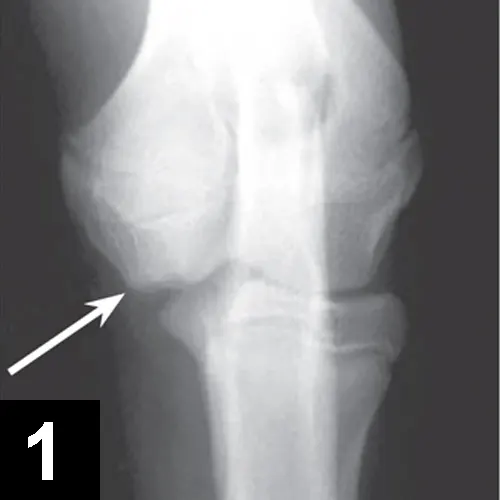

• Orthogonal radiographs may confirm diagnosis, especially with OCD lesions (Figures 1 and 2).

FIGURE 1

Craniocaudal view of an elbow with OCD lesion (arrow).